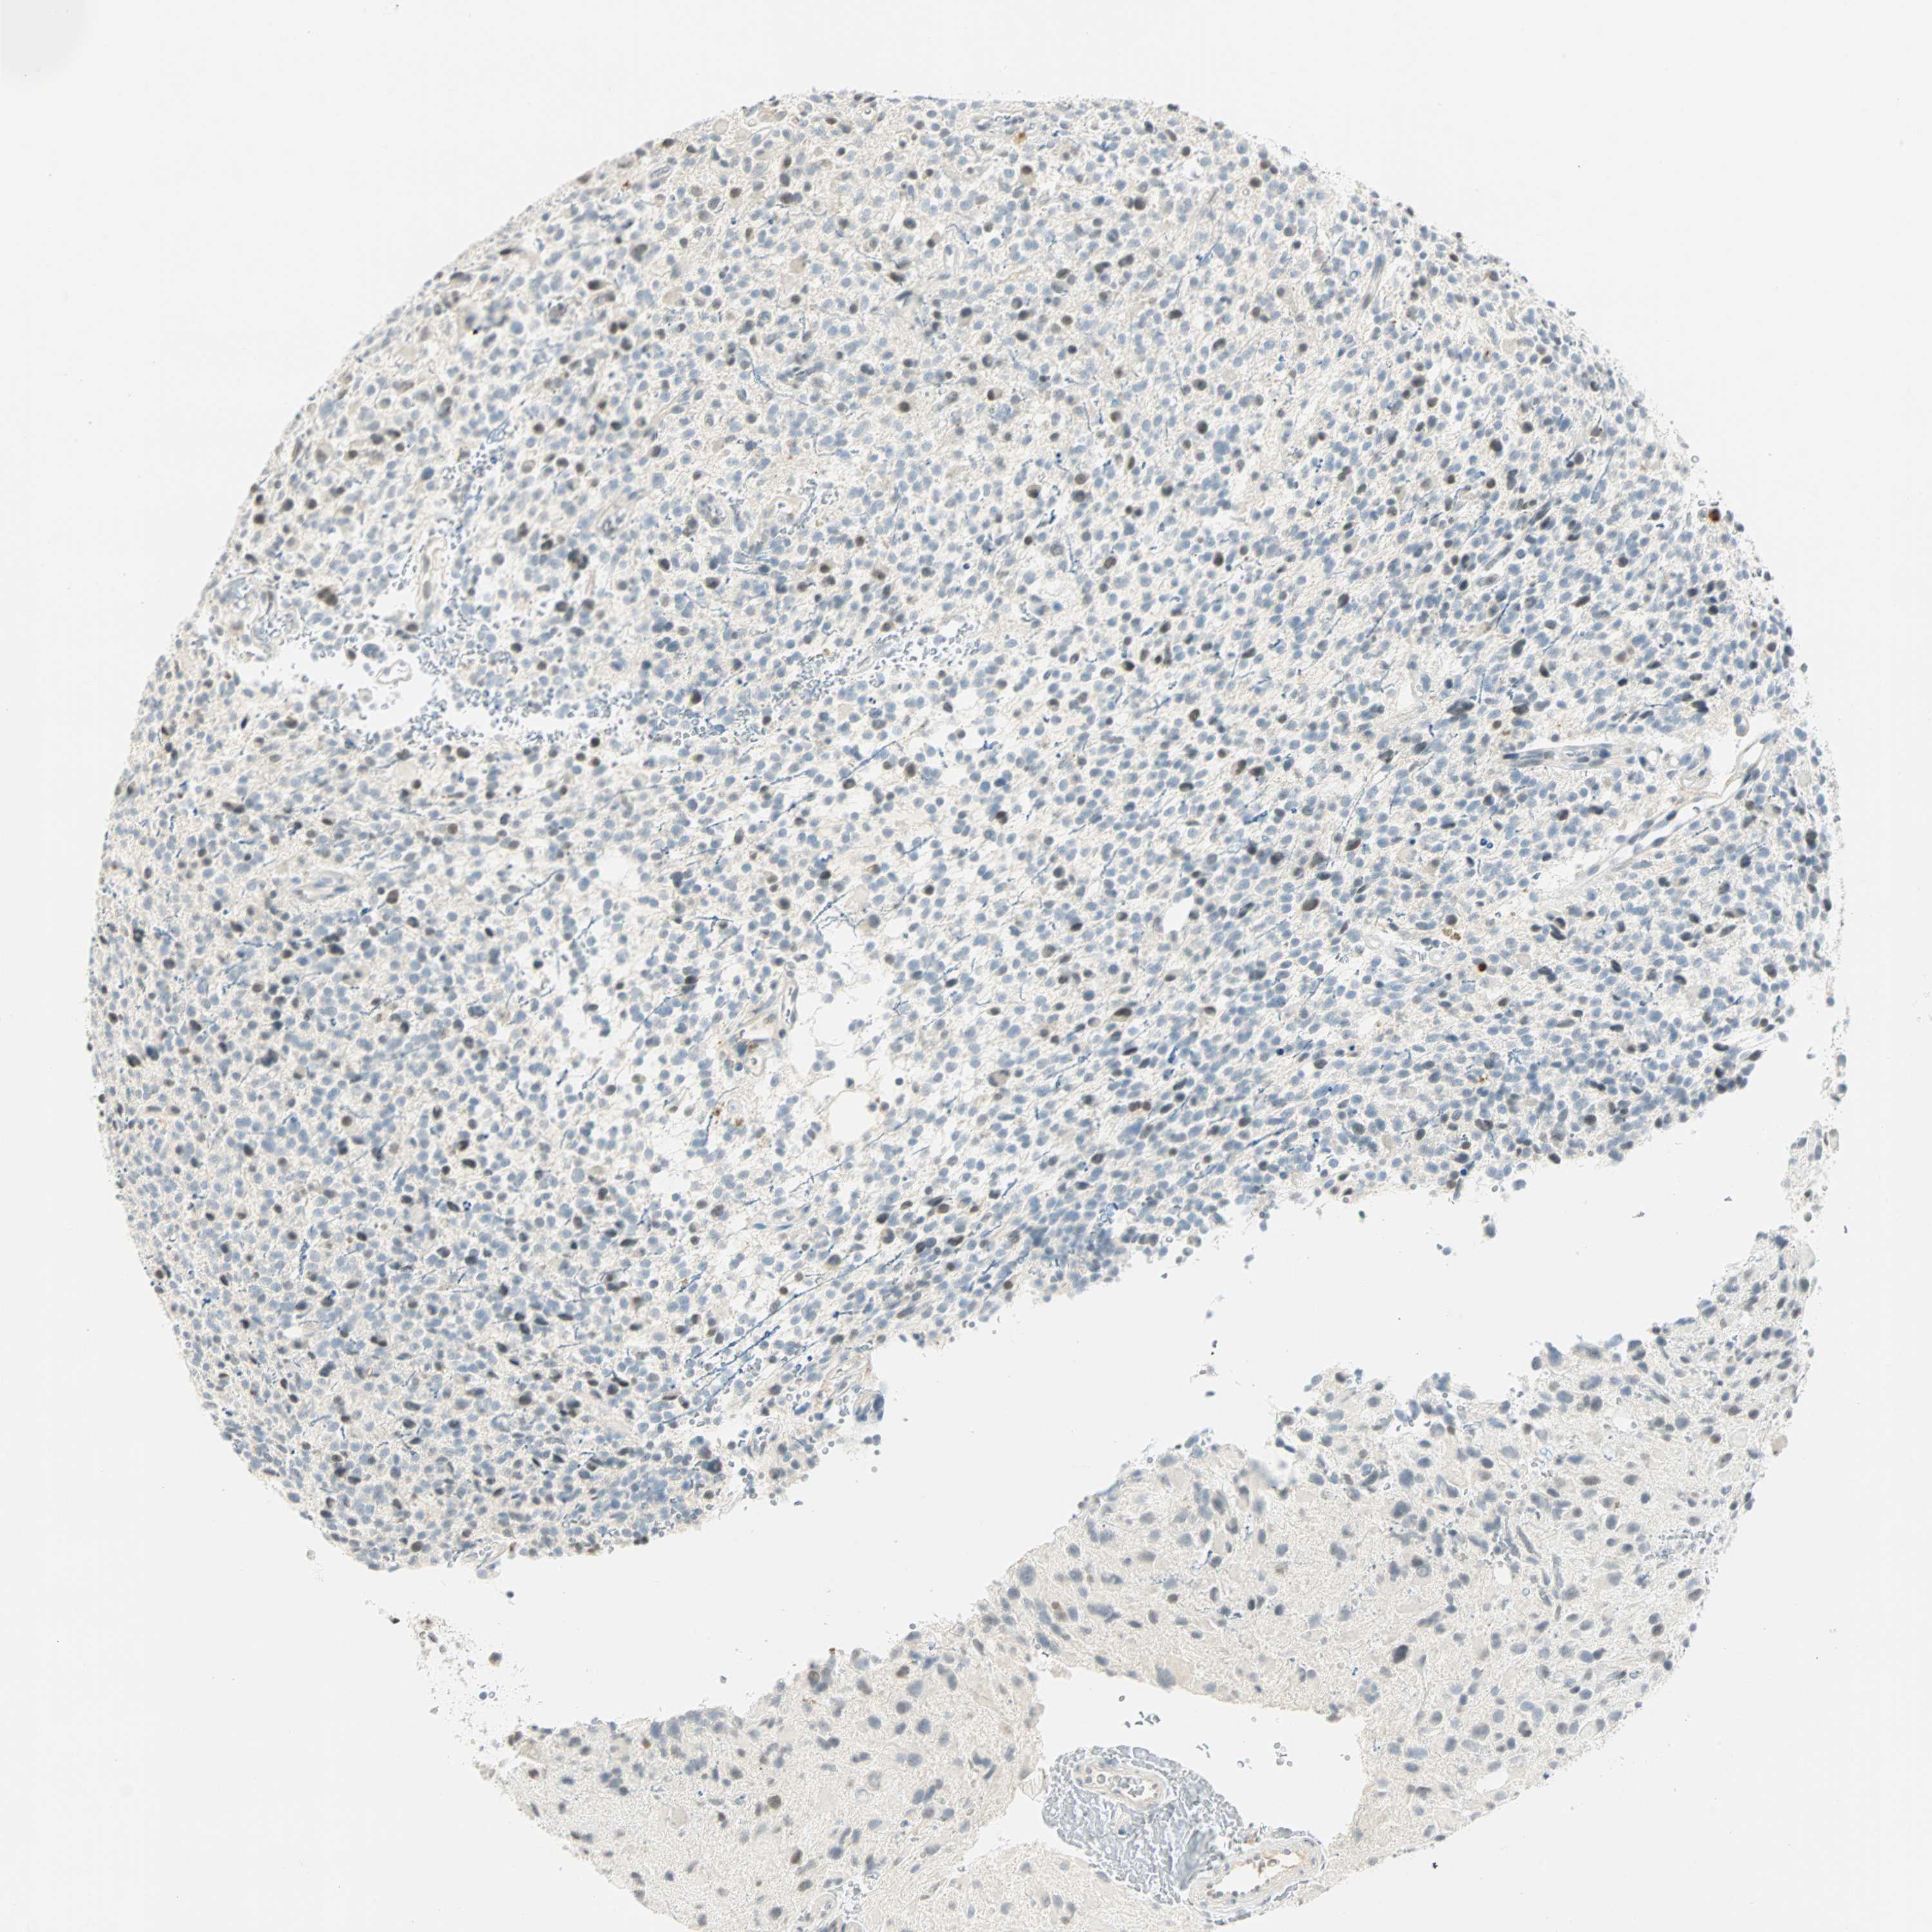

GLIOMA - Protein expressioni

A mouse-over function shows sample information and annotation data. Click on an image to view it in a full screen mode. Samples can be filtered based on level of antibody staining by selecting one or several of the following categories: high, medium, low and not detected. The assay and annotation is described here.

Note that samples used for immunohistochemistry by the Human Protein Atlas do not correspond to samples in the TCGA dataset.

Antibody stainingi

Antibody staining in the annotated cell types in the current human tissue is reported as not detected, low, medium, or high, based on conventional immunohistochemistry profiling in selected tissues. This score is based on the combination of the staining intensity and fraction of stained cells.

Each image is clickable and will lead to virtual microscopy that enables deeper exploration of all samples and also displays staining intensity scores, fraction scores and subcellular localization as well as patient and tissue information for each sample.

Antibody HPA067203

Antibody CAB008094

Antibody CAB069409

Staining

High

Medium

Low

Not detected

Intensity

Strong

Moderate

Weak

Negative

Quantity

>75%

75%-25%

<25%

None

Location

Nuclear

Cytoplasmic/membranous

Cytoplasmic/membranous,nuclear

Glioma, malignant, Low grade

Glioma, malignant, High grade